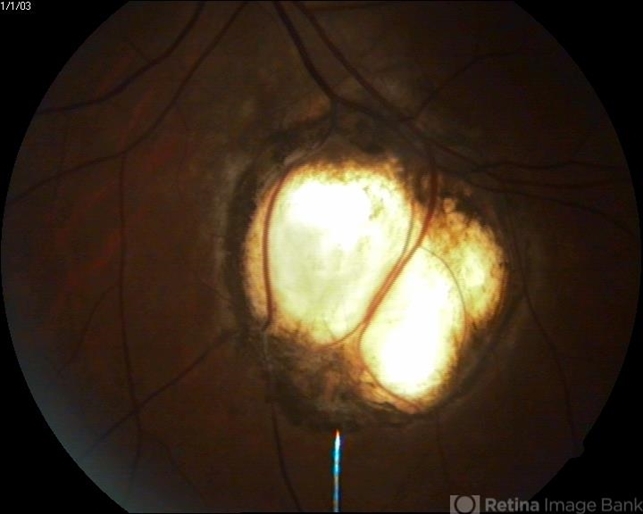

- choroidal coloboma

- A 24-year-old female found to have this coloboma when she presented to us for routine check up, her vision is 20/20 as it excluded disc and macula